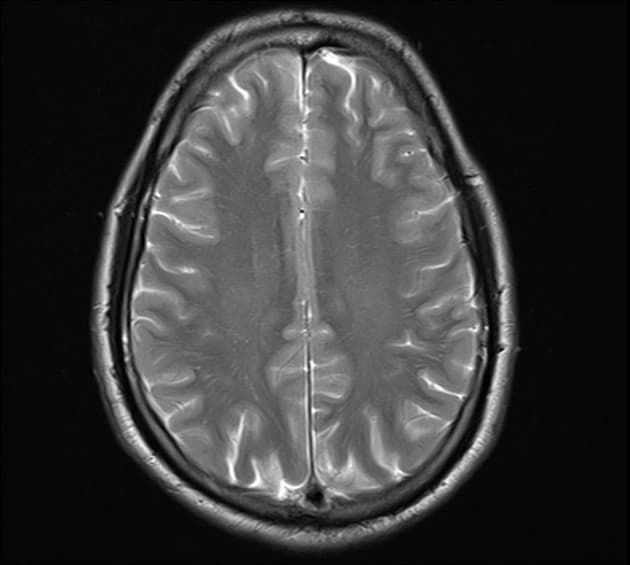

- Ghi nhận bất thường tín hiệu đối xứng hai bên (bilateral symmetrical signal abnormality) tại vị trí nhân bèo (putamen), biểu hiện tăng tín hiệu (hyperintense) trên các chuỗi xung T2W/FLAIR và có hạn chế khuếch tán (restricted diffusion) trên DWI.

- "Hạn chế khuếch tán đối xứng ở nhân bèo trên MRI là dấu hiệu sớm quan trọng trong ngộ độc cấp tính."

Ngộ độc methanol là một cấp cứu y khoa nghiêm trọng do uống phải rượu bị tạp nhiễm. Độc tính chủ yếu do chất chuyển hóa của nó là axit formic, chất này ức chế cytochrome c oxidase của ty thể, dẫn đến thiếu oxy tế bào. Về mặt hình ảnh, dấu hiệu điển hình là hoại tử nhân bèo đối xứng hai bên, có thể kèm theo xuất huyết. Tổn thương chất trắng dưới vỏ và dây thần kinh thị (bệnh lý thần kinh thị) cũng thường gặp. Biểu hiện lâm sàng thường bao gồm một giai đoạn tiềm tàng, sau đó là nhiễm toan chuyển hóa, rối loạn thị giác từ nhìn mờ đến mù lòa và các mức độ suy giảm thần kinh khác nhau.